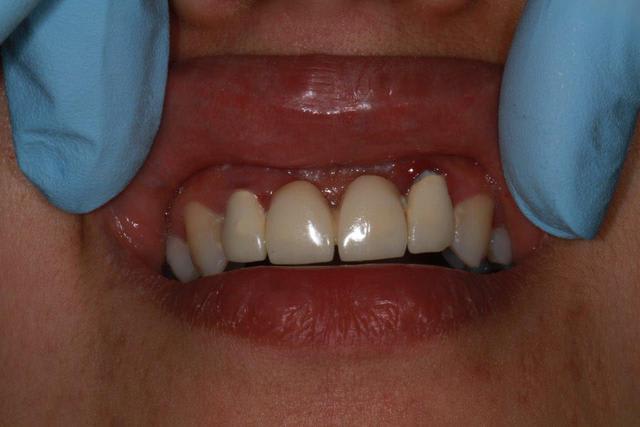

Patiente sympa, 30 ans, un bridge ceramo-métal fait il y a 10 ans, en fin de vie.

Les endo et les IC dans les 12-22 sont sublimes...et ça a durer 10 ans....incroyable...Il y a pas de la paro aussi ?

Oui et un peu particulier au niveau de 12/22, le bridge a été fait suite à un accident sur 11/21, mais soit l'accident était grave, soit le confrère Marocain, un peu pressé.